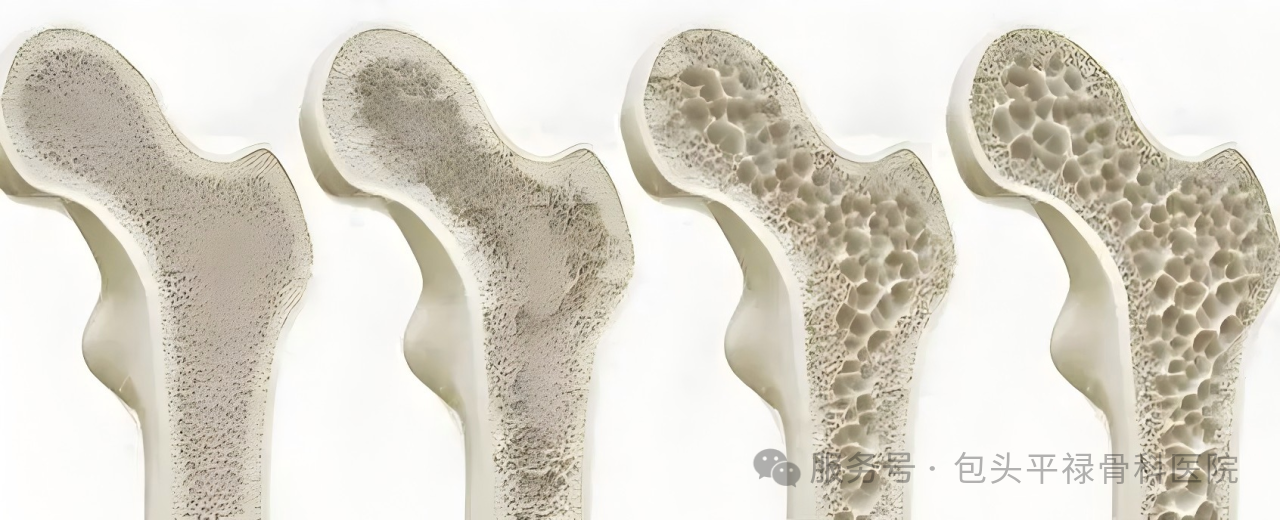

骨质疏松症是一种代谢性骨病,主要表现为骨量减少、骨组织微结构破坏和骨脆性增加,骨折风险显著增高。患者早期通常没有明显症状,往往骨折后才发现,因此被称为“沉默的骨骼杀手”。

随着骨质疏松加重,脊柱可能发生变形,如身高缩短、驼背等。据统计,老年人骨质疏松时每节椎体可缩短约2毫米,导致身高平均减少3-6厘米

示意图片来源于网络,侵删